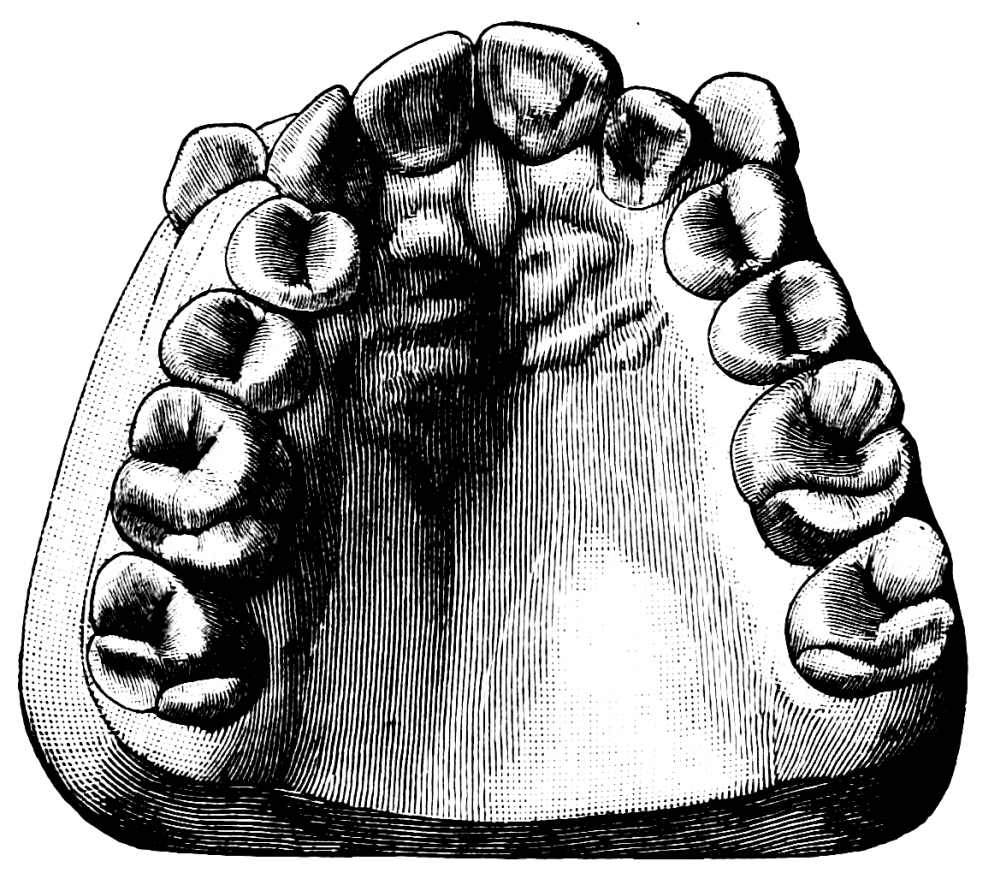

A correct acquaintance with the disposition of the alveoli of the teeth is of importance for skilful and successful operating. Fig. 15 gives a general idea of the appearance of the alveoli, but it is needless to say that a full knowledge can only be really obtained by a careful study of the bones themselves; by this means, too, some idea of the strength of different portions of the alveolar borders can be obtained—a matter of some moment when applying force in the process of removing a tooth from its socket. The points to be specially noted in the maxilla are the thinness of the outer alveolar wall as compared with the inner, the prominence of the canine socket, and the cancellous character of the bone in the region of the third molar. In the mandible the outer alveolar border will be seen to be thinner than the inner, with the exception of that portion in the region of the{13}

third, and often of the second molar; another fact worthy of attention is that at the posterior portion{14} of the socket of the third molar the bone is moderately dense.